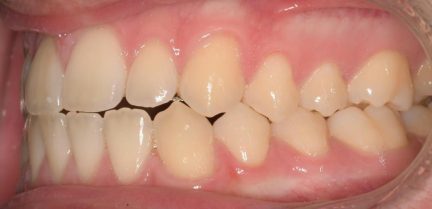

Classe III, articulé croisé postérieur, articulé croisé antérieur, occlusion bout-à-bout, articulation ouverte, arcades étroites, arcades asymétriques, déviation médiane maxillaire, déviation médiane mandibulaire, décalage médian, chevauchement, rotations

État initial